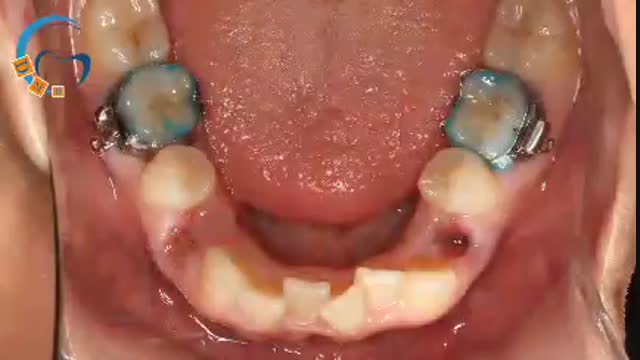

کشیدن دندان گاها برای بیماران ارتودنسی و با هدف مرتب کردن دندان ها اجتناب ناپذیر می‌باشد. با این حال لازم است مطلع باشید که جای هیچ گونه نگرانی بابت فضای خالی دندان‌های کشیده شده نمی‌باشد، چراکه این فضا برای مرتب سازی دیگر دندان‌ها مورد استفاده قرار خواهد گرفت و تا پایان درمان این فضا کاملا بسته خواهد شد.